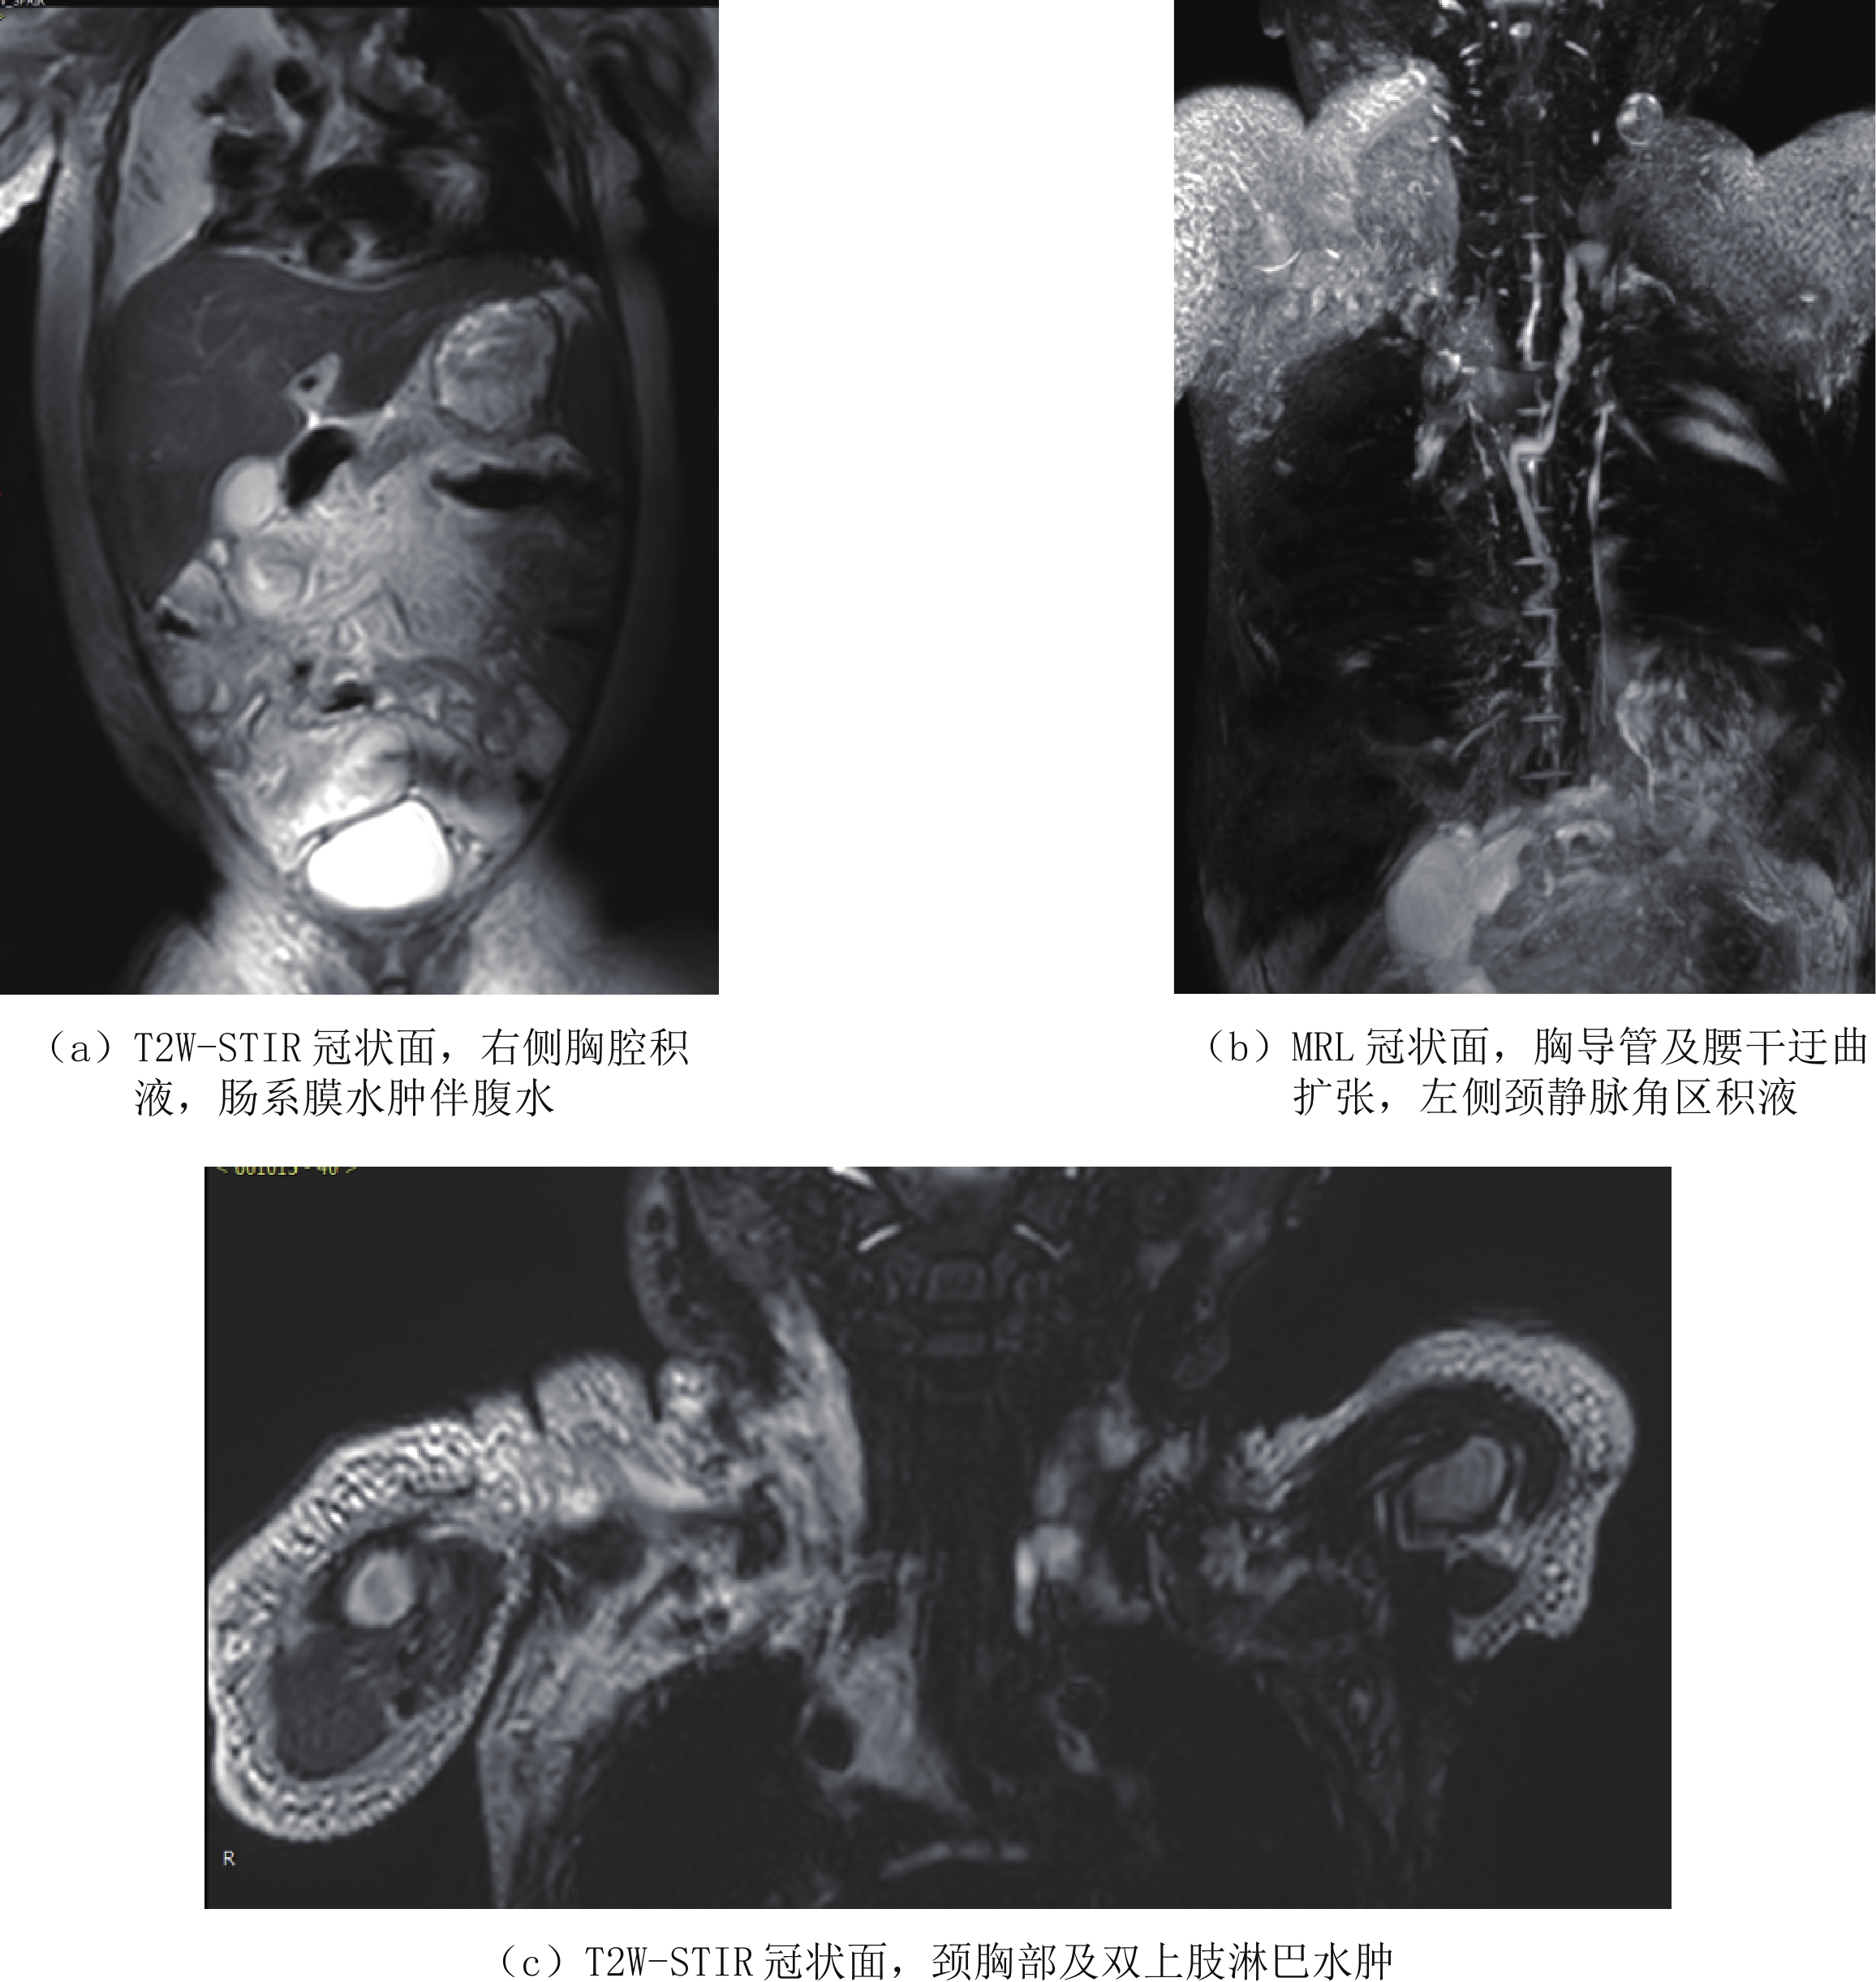

图 1 男,6天。以"生后气促6天"入院。左侧大量胸腔积液,胸水常规检查提示白细胞升高,胸水内甘油三酯含量高—新生儿乳糜胸Figure 1. Male, 6 days old, admitted to hospital with "postnatal shortness of breath for 6 days". Large amount of pleural effusion of the left side. Routine examination of the pleural effusion indicates elevated leukocytes and high triglyceride content in pleural effusion-neonatal chylothoraxCLFDs新生儿期或婴幼儿期可以表现为乳糜胸、乳糜腹和淋巴水肿,可以进行性加重,死亡率高。CLFDs分为先天性和继发性。先天性CLFDs主要是由于胸导管或中央淋巴系统发育不良所致,通过DCMRL检查腹膜后、脊柱周围没有正常的胸导管或中央淋巴系统的显示,对比剂通过异常部位的侧枝淋巴管回流。继发性CLFDs是由于各种原因所致的中心静脉压升高,如继发于肺动脉高压、完全性肺静脉异位引流以及中心静脉血栓等,导致淋巴液回流受阻,可行磁共振淋巴管造影(MRL)证实(图2),影像表现为胸导管或中央淋巴系统迂曲扩张,走行分布未见异常,颈部、胸壁、肠系膜水肿,伴胸腔和或腹腔积液。

塑形性支气管炎(plastic bronchitis)可以继发于淋巴管发育异常,当中心静脉压升高如完全肺静脉异位引流、上腔静脉肺动脉连接手术后(fontan循环)导致胸部淋巴回流受阻,锁骨上区、纵隔、支气管周围及肺组织内淋巴管内压力增高而扩张,并使蛋白质含量较高的乳糜液漏入气道,形成支气管管型引起的气道阻塞。文献报道利用DCMRL检查可以证实乳糜液漏入气道,DCMRL表现为对比剂自肺门沿着肺部气管支气管树呈放射状分布,肺门区对比剂浓聚,且胸导管及中央淋巴系统迂曲扩张(图3),并可指导淋巴管异常的介入治疗[9-10]。

图 3 塑形性支气管炎患儿的动态增强磁共振淋巴管造影(DCMRL),双胸导管(短箭头)和异常肺淋巴流(长箭头)[9]Figure 3. DCMRL of the patient with PB, demonstrating double Thoracic duct (arrowheads) and abnormal pulmonary lymphatic flow (arrows)2.2 淋巴管扩张症

图 3 塑形性支气管炎患儿的动态增强磁共振淋巴管造影(DCMRL),双胸导管(短箭头)和异常肺淋巴流(长箭头)[9]

Figure 3. DCMRL of the patient with PB, demonstrating double Thoracic duct (arrowheads) and abnormal pulmonary lymphatic flow (arrows)